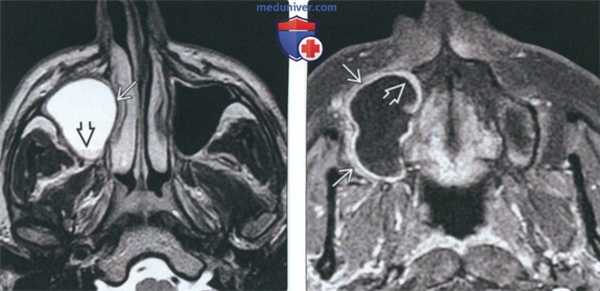

(Слева) На аксиальной МРТ (Т2 ВИ FSE) визуализируется ОКК, заполняющая правую верхнечелюстную пазуху и смещающая медиальную стенку. Киста имеет гиперинтенсивный сигнал с небольшим включением с сигналом промежуточной интенсивности (дебрис). Т2 сигнал в ОКК варьирует в зависимости от количества дебриса в ней.

(Справа) На аксиальной MPT (Т1 ВИ С+ FS) у этого же пациента определяется волнообразное расширение альвеолярного отростка верхней челюсти. Определяется участок с сигналом низкой интенсивности с тонким контрастирующимся «ободком» на периферии. Солидные объемные образования отсутствуют.